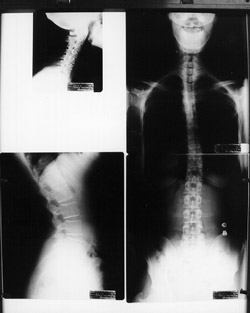

Spinal X-rays may be taken depending on your age, and situation. There are many reasons why we would not take x-rays on certain patients including pregnancy, most children, recent usable spinal x-rays and some other various situations. Aside from these situations, x-rays are a common part of the examination process when looking for vertebral subluxations. X-rays give us important information including the position of the spinal bones, and the quality of the spine and safety of adjusting it. X-rays also tell us the relative length of time subluxations may have been involved in your spine. Commonly, most patients receive three spinal x-rays at the beginning of care.

With this important information we can make a more accurate determination of the type of adjustments your spine needs as well as the ongoing frequency of your care. Your x-rays will be explained to you and covered in detail at your Patient Orienation. You will be scheduled for your Patient Orienation within a few days of your initial visit. This visit is your most important visit and may take up to one hour. It is at your Patient Orienation that we will show you the unique concerns your x-rays contain, and help you understand the neurological implcations related to the films you will be viewing at this appointment.